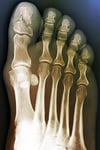

Если есть подозрение на определенные повреждения, показана рентгенография.

ZEPHYR/SCIENCE PHOTO LIBRARY

Проводить рентгенографию обычно не требуется, если нет подозрения на ротационную деформацию или повреждение сустава, или на повреждение проксимальной фаланги большого пальца (большой палец стопы), поскольку лечение, даже если перелом имеется, не изменяется. Когда рентгенография показана, ее проводят в передне-задней, боковой, косой проекциях для каждого пальца.

При подозрении на ротационную деформацию или повреждение сустава или при наличии повреждения проксимальной фаланги большого пальца стопы необходимо провести рентгенографию в передне-задней, боковой и косой проекциях; в остальных случаях рентгенограммы обычно не являются необходимыми, поскольку лечение при наличии или отсутствии перелома не меняется.